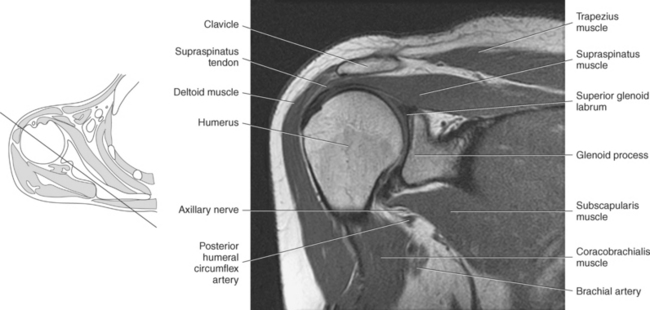

Figure 9.10 Sagittal oblique, T1-weighted MR scan of shoulder.

Key: cor, Coracoid process; cl, clavicle; sup, supraspinatus; ac, acromion; inf, infraspinatus; de, deltoid; tm, teres minor; gl, glenoid; sub, subscapularis; h, humerus; grt, greater tubercle; sc, scapula; glf, glenoid fossa; hh, humeral head.